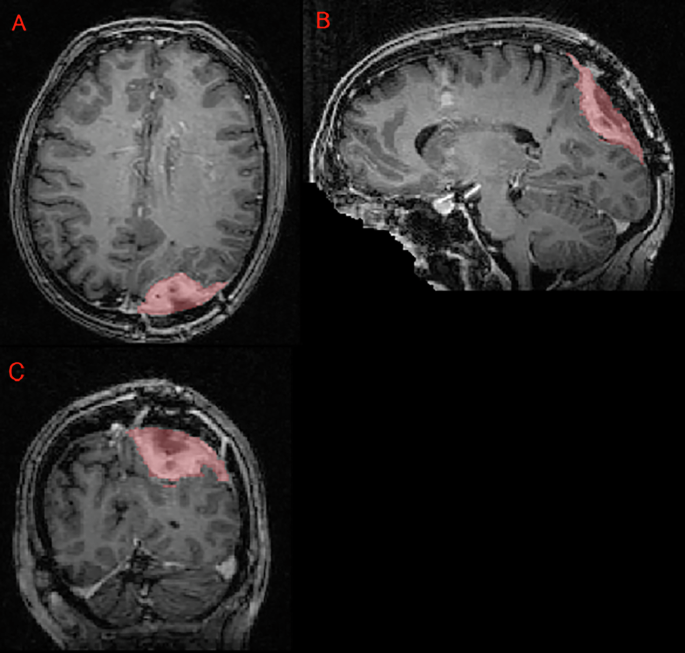

The imaging dataset includes exclusively 3D T1c brain MRI scans in native acquisition resolution in either the intact (Fig. 1) or postoperative setting (Fig. 2, 3), which mimics the data available for most radiotherapy planning. While additional sequences such as T1-weighted, T2-weighted, T2-FLAIR, and computed tomography are sometimes used in clinical workflows, these were not consistently available nor required for RT planning at all centers and were therefore not included in the dataset.

Panels A, B, and C showing a postoperative left parietal meningioma target volume (red) in the axial, sagittal, and coronal planes, respectively, as delineated by the treating institution.